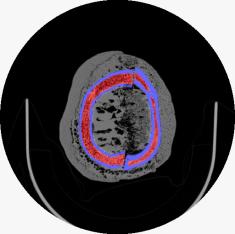

These CT slices are of the Case 0102 phantom cranium. Views were selected form the transverse, coronal, and sagital planes.